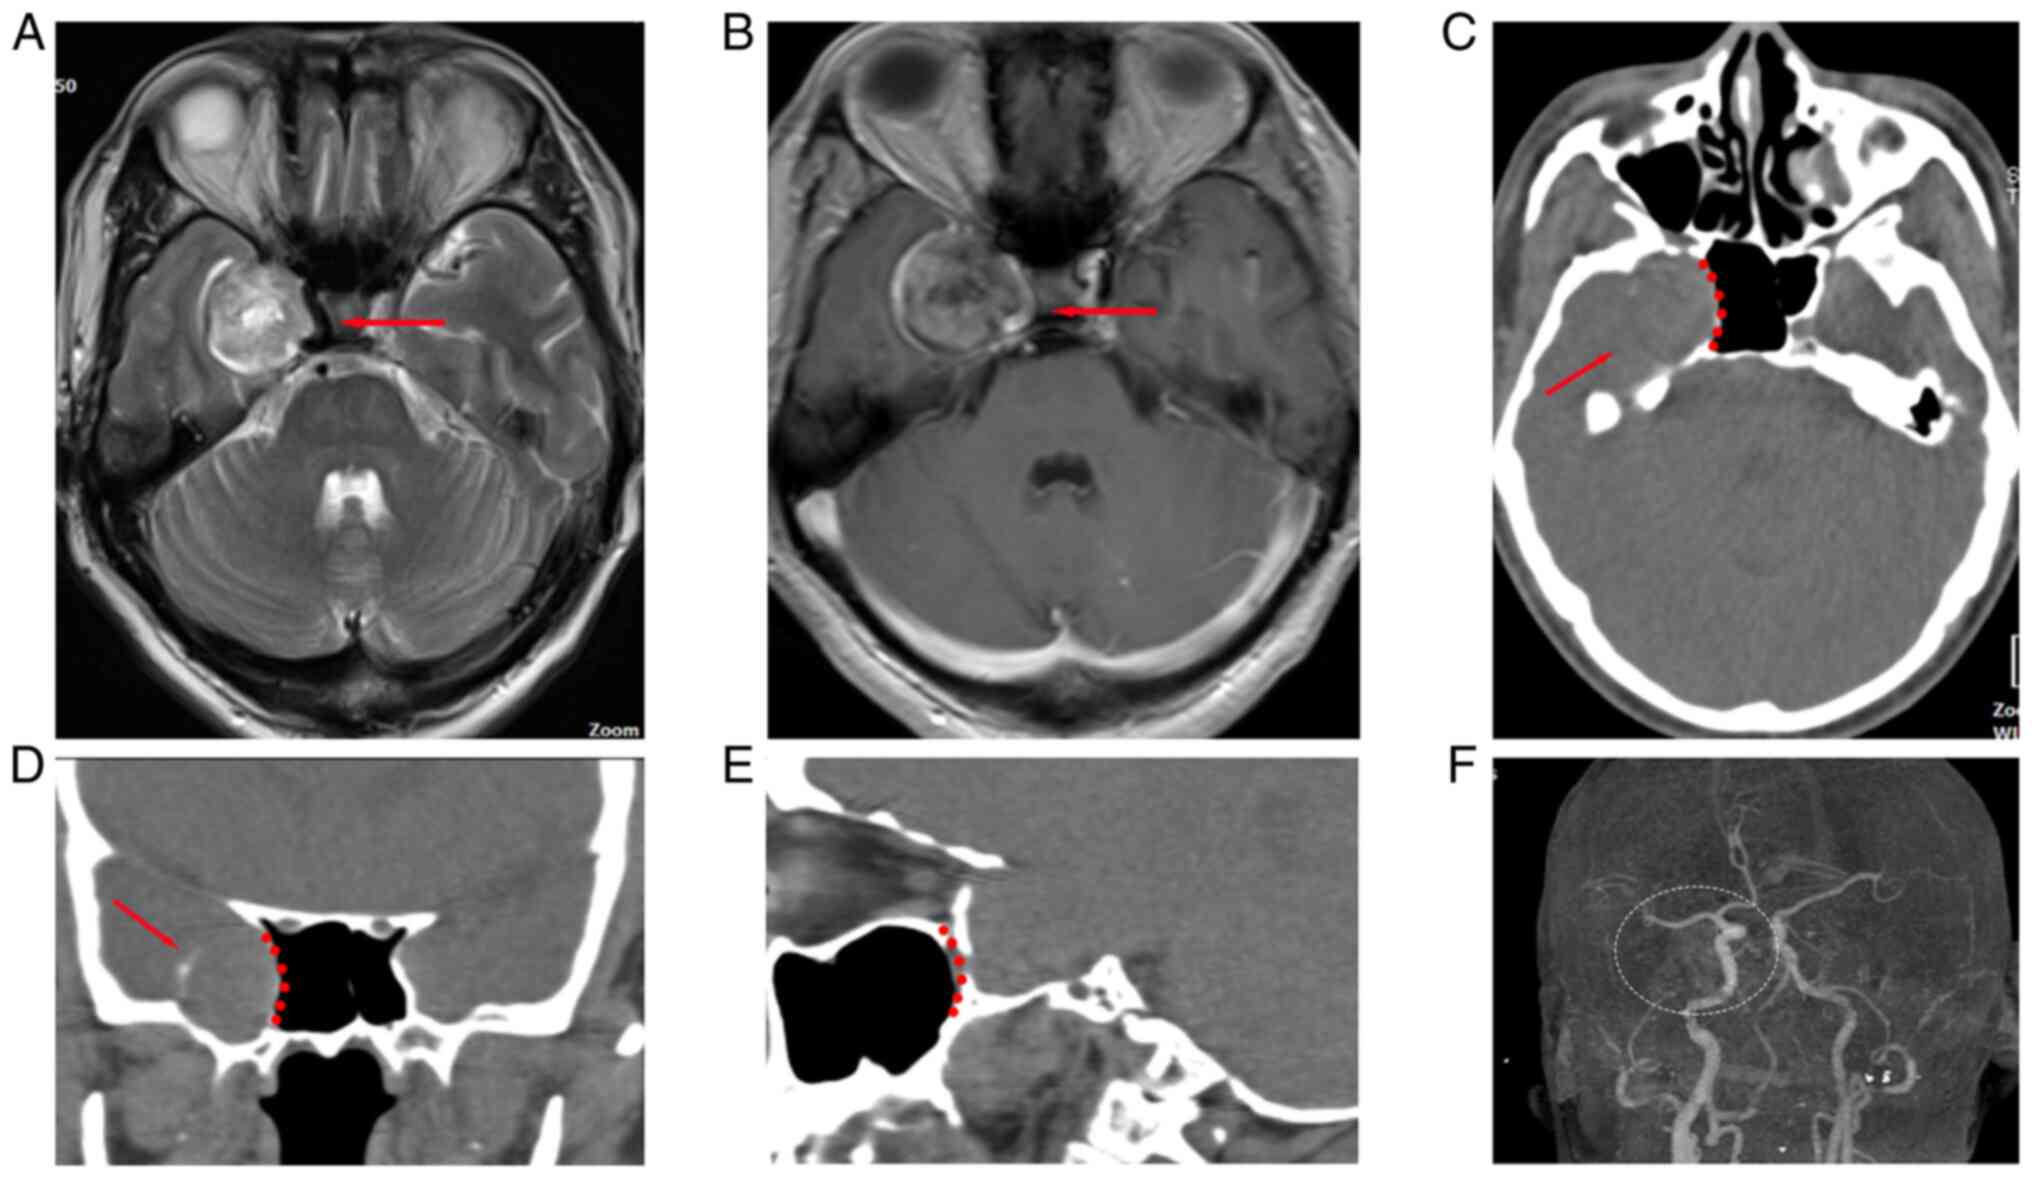

A 59-year-old man with a 2-year history of progressive intermittent headaches without other noteworthy medical or family history was admitted to the Department of Neurosurgery, Chongqing General Hospital (Chongqing, China) in May 2019. A neurological test showed no abnormalities. Radiography indicated that there was a spherical lesion located in the right middle fossa of the cranium with eggshell calcification (Fig. 1) that was diagnosed as a TS located in Meckel's cave. The right cavernous sinus and internal carotid artery (ICA) that were adjacent to the lesion were compressed and displaced. CT angiography (CTA) excluded vascular abnormalities.

Figure 1

Pre-operative imaging of a TS located in the right middle cranial fossa. (A) Transverse section of the T2-weighted image indicated the position of the TS and the red arrow indicates the flow void in the ICA, which was suppressed by TS. (B) Enhanced transverse section of magnetic resonance imaging showed the direct relationship between the TS and ICA (red arrow indicates the ICA enhanced by contrast agent). (C) Transverse section of the CT scan showed the relationship among the TS, the posterior wall of the maxillary sinus and the lateral wall of the sphenoid sinus (red dotted line represents the lateral wall of the sphenoid sinus; red arrow indicates the eggshell calcification). (D) Coronal section of the CT scan showed that the TS was closely adjacent to the lateral wall of the sphenoid sinus (red dotted line represents the lateral wall of the sphenoid sinus and the red arrow indicates eggshell calcification). (E) Sagittal section of the CT scan showed that the TS was closely adjacent to the posterior wall of the maxillary sinus (red dotted line represents the posterior wall of the maxillary sinus). (F) Cerebral angiography showed that cerebral vessels were in a normal state excluding vascular abnormalities. (white dotted zone indicates the position of the tumor). CT, computed tomography; ICA, intracranial carotid artery; TS, trigeminal schwannoma.